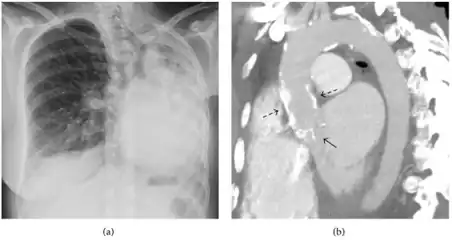

A fibrothorax can typically be diagnosed by taking an appropriate medical history in combination with the use of appropriate imaging techniques such as a plain chest X-ray or CT scan.[3] These imaging techniques can detect fibrothorax and pleural thickening that surround the lungs.[7] The presence of a thickened peel with or without calcification are common features of fibrothorax when imaged.[3] CT scans can more readily differentiate whether pleural thickening is due to extra fat deposition or true pleural thickening than X-rays.[3]

If a fibrothorax is severe, the thickening may restrict the lung on the affected side causing a loss of lung volume.[7] Additionally, the mediastinum may be physically shifted toward the affected side.[3] A reduction in the size of one side of the chest (hemithorax) on an X-ray or CT scan of the chest suggests chronic scarring.[6] Signs of the underlying disease causing the fibrothorax are also occasionally seen on the X-ray.[6] A CT scan may show features similar to those seen on a plain X-ray.[7] Lung function testing typically demonstrates findings consistent with restrictive lung disease.[6]

Autopsy specimen showing extensive pleural fibrosis